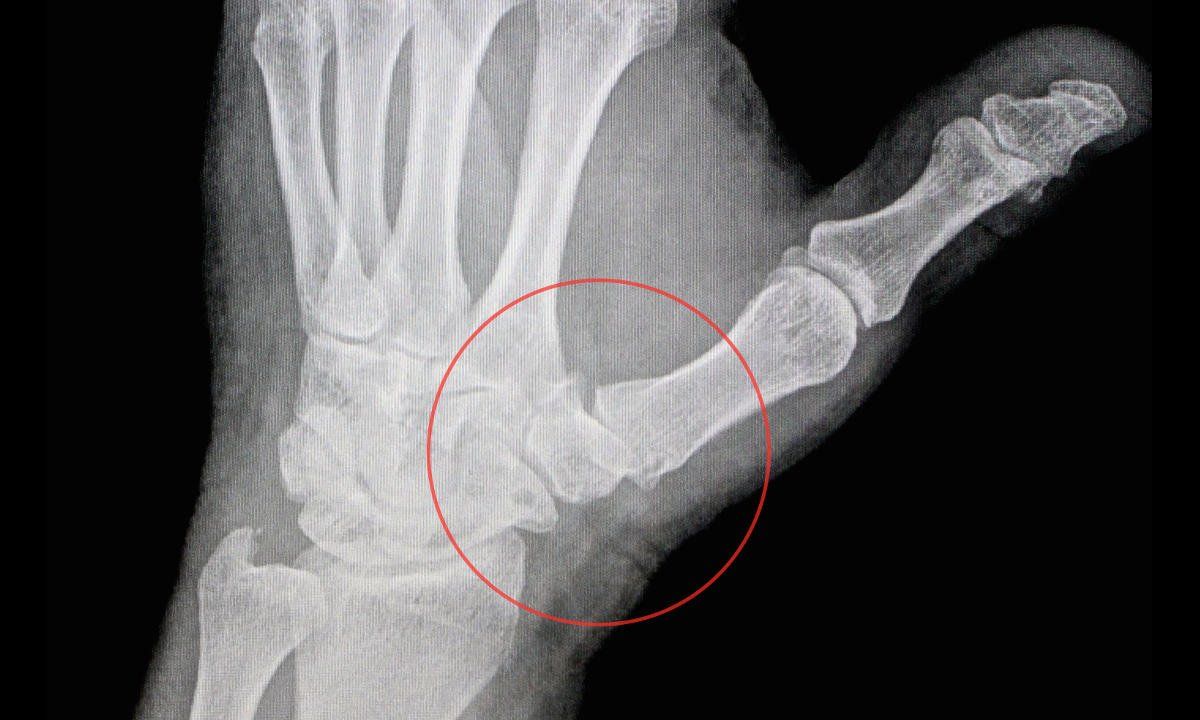

● Kiểm tra bằng các kỹ thuật chẩn đoán hình ảnh như chụp X-quang để xem xét những dấu hiệu của viêm khớp ngón tay, bao gồm các cựa xương, sụn bị mòn, mất khoảng trống của khớp,...